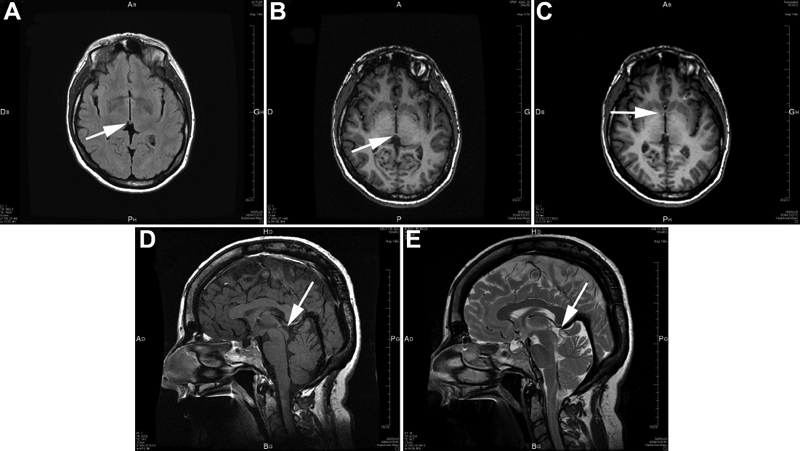

Figure 6. Brain MRI abnormalities in patient IV-5 from family F with the PAX6 serine 74 to glycine mutation

We show different MRI views of patient IV-5 from family F. A, B, and C correspond to MRI horizontal views, while D and E correspond to MRI sagittal views. MRI in A shows a small structure that might correspond to the habenula (arrow). MRI in B, D, and E reveals the absence of the pineal gland (arrow). MRI in C shows hypoplasia of the anterior commissure of the brain (arrow).